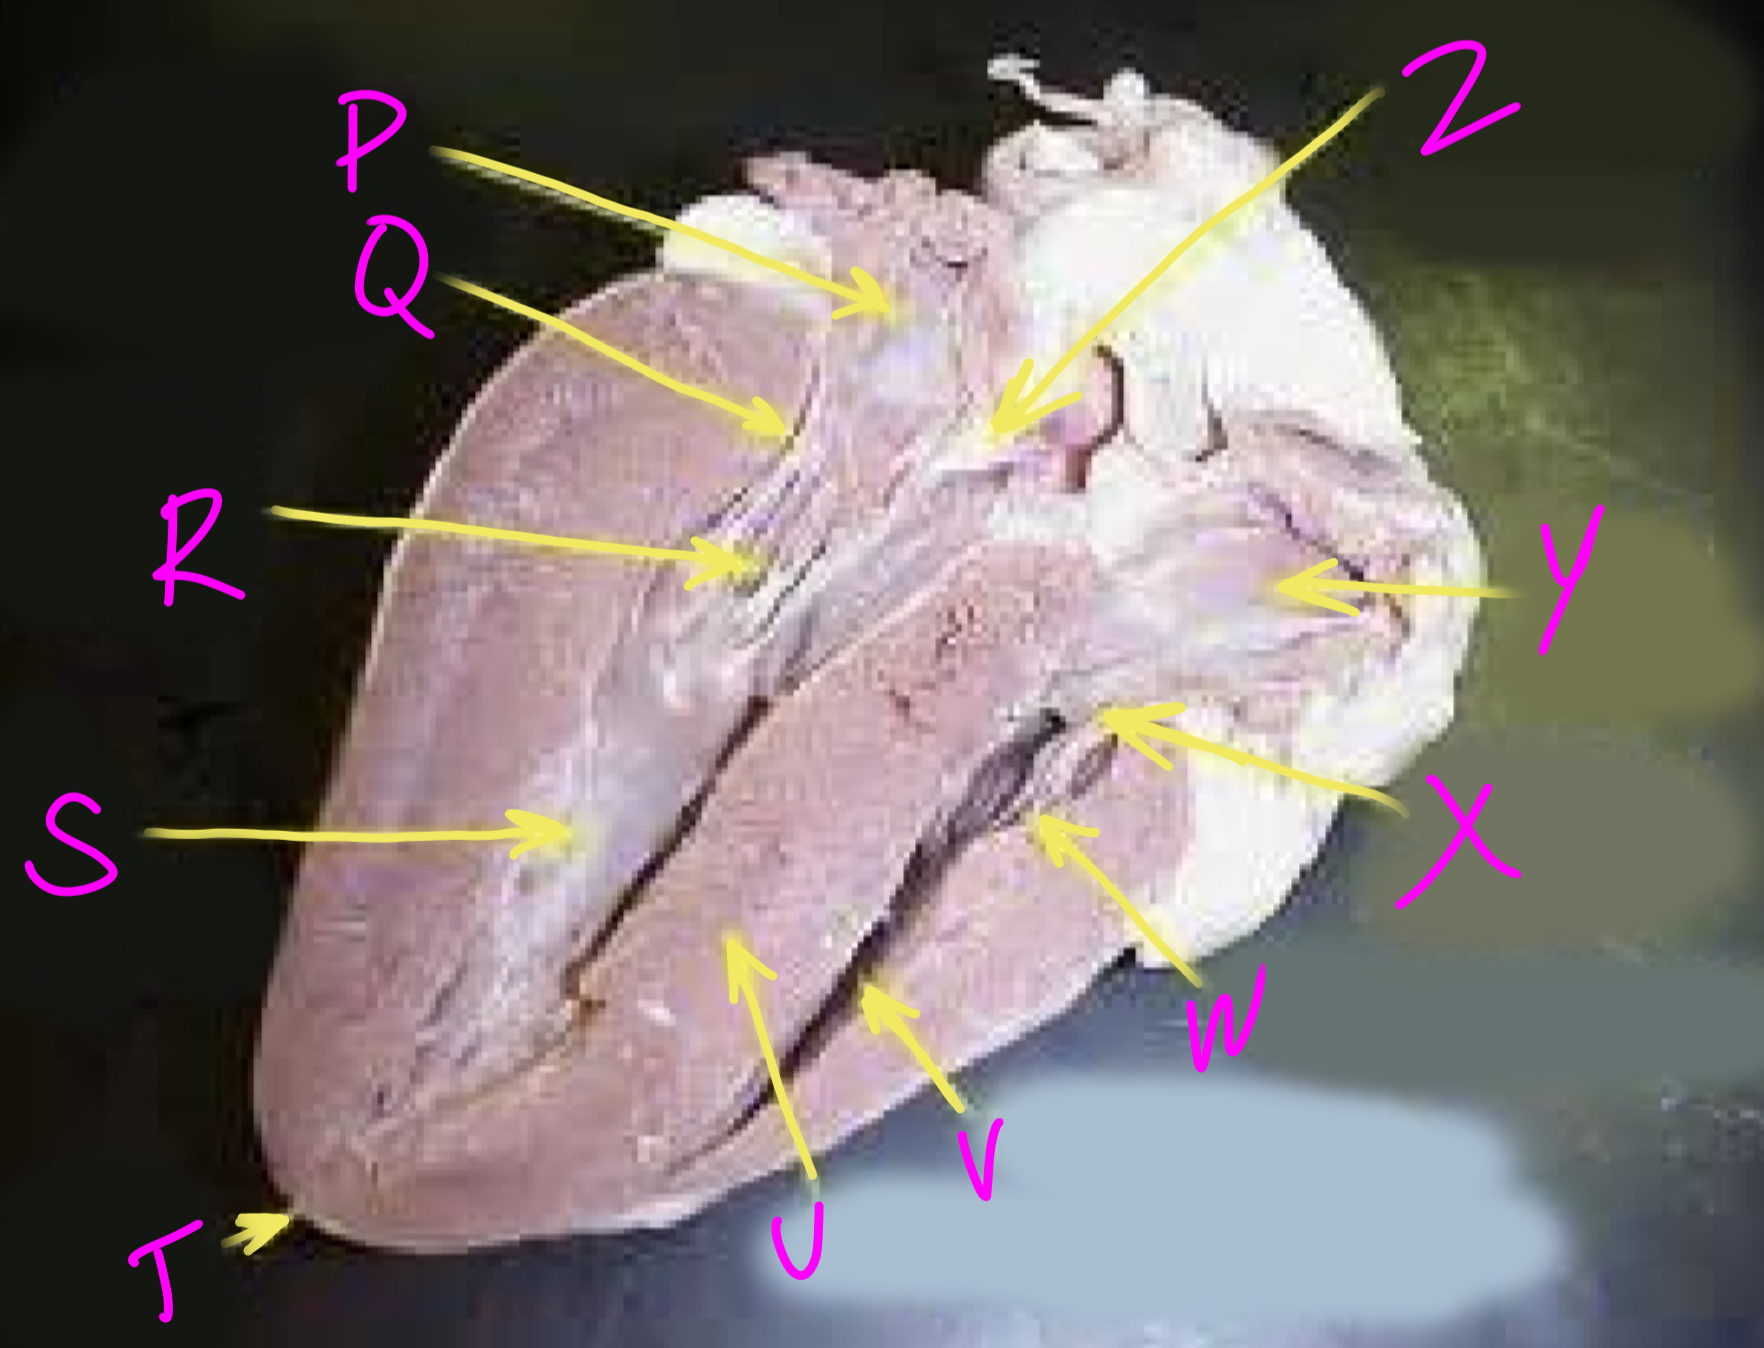

P

Left atrium

Q

Bicuspid valve - allows blood to flow from the left ventricle to the aorta

R

Right chordae tendinae - hold AV valves in place

S

Left ventricle

T

Apex - pumps blood out of the ventricles

U

Interventricular septum - divides the right and left ventricles

V

Right ventricle

W

Left chordae tendinae - hold AV valves in place

X

Tricuspid valve

Y

Right atrium

Z

Aortic semilunar valve - prevent backflow